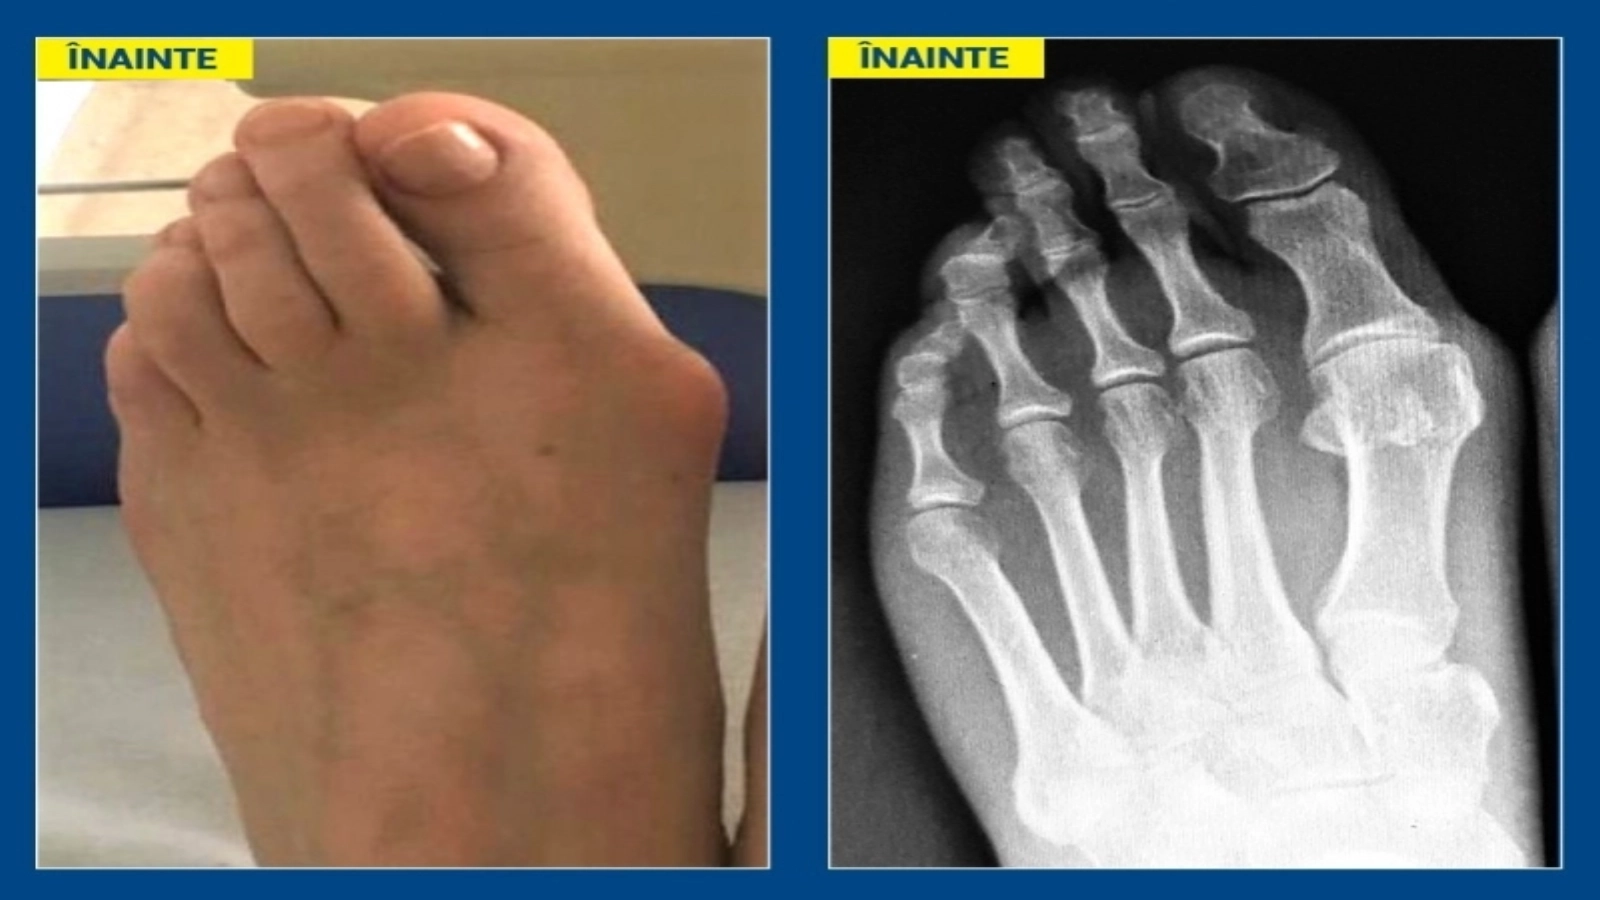

Monturile sau hallux valgus sunt deformări ale antepiciorului, apărute prin devierea osului de la baza halucelui (degetul mare) către interior, astfel încât capul acestui os proemină sub piele („montul”), în timp ce degetul mare este deviat către lateral, către degetele mici, pe care le împinge și, ulterior, le forțează să se „încalece”.

Corectarea diformității și a problemelor legate de aceasta (dureri, disconfort la purtarea pantofilor obișnuiți etc) poate fi făcută printr-o intervenție chirurgicală, de către un medic ortoped. Orice alte metode pot cel mult să întârzie evoluția deformării și să ajute la atenuarea durerilor.

Intervenția de înlăturare a monturilor este una rapidă și nedureroasă, pacientul putând să revină la activitățile cotidiene chiar începând de a doua zi. Trebuie însă să poarte sandale ortopedice speciale încă din prima zi după operație, timp de minimum o lună de zile.